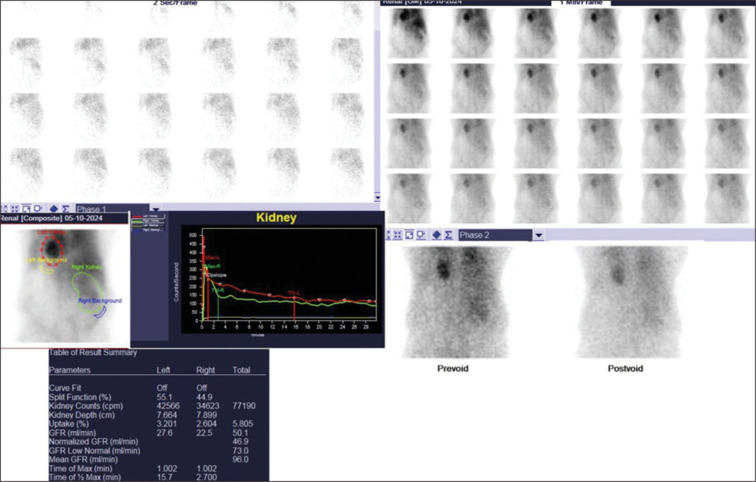

胸内肾非常罕见,在所有肾异位中发病率最低。我们报告的情况下,70岁的男性谁被转介二乙烯三胺五乙酸(DTPA)扫描作为术前工作的一部分,为右肾肿块。腹部超声检查错误报告左肾位置正常。99mTc-DTPA肾脏扫描联合单光子发射计算机断层扫描-计算机断层扫描显示左肾异位(胸腔内)肾小球滤过率受损。18-氟脱氧葡萄糖正电子发射断层扫描-计算机断层扫描图像显示软组织肿块完全取代右肾并转移到双侧肺。本病例再次强调了核医学成像在诊断和评价胸内肾功能中的重要性。

Intrathoracic kidney is very rare and has the lowest prevalence among all renal ectopias. We report the case of a 70-year-old male who was referred for diethylenetriaminepentaacetic acid (DTPA) scan as a part of presurgical work-up for a right renal mass. PriorUltrasonography abdomen incorrectly reported left kidney as normal in location. 99mTc-DTPA renal scan combined with single-photon emission computed tomography - computed tomography revealed impaired global glomerular filtration rate with left kidney in ectopic (intrathoracic) location. 18-fluorodeoxyglucose positron emission tomography-computed tomography images revealed a soft tissue mass completely replacing the right kidney with metastases to bilateral lungs. This case reemphasizes the importance of nuclear medicine imaging in diagnosis and evaluation of the renal function of the intrathoracic kidney.